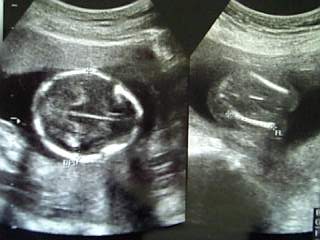

左→へその緒が見えます。

右→万歳してる??

とにかくよく動くので、なかなかよい写真は撮れません。

それにしてもまだ胎動は感じれないハハです。

看護婦さんや先生に、「もう動くのわかる?」と聞かれたけど、全くw。

ただ、お腹になにかが居る気配は感じるようになったケド。

胎動、そろそろかな?楽しみだな♪